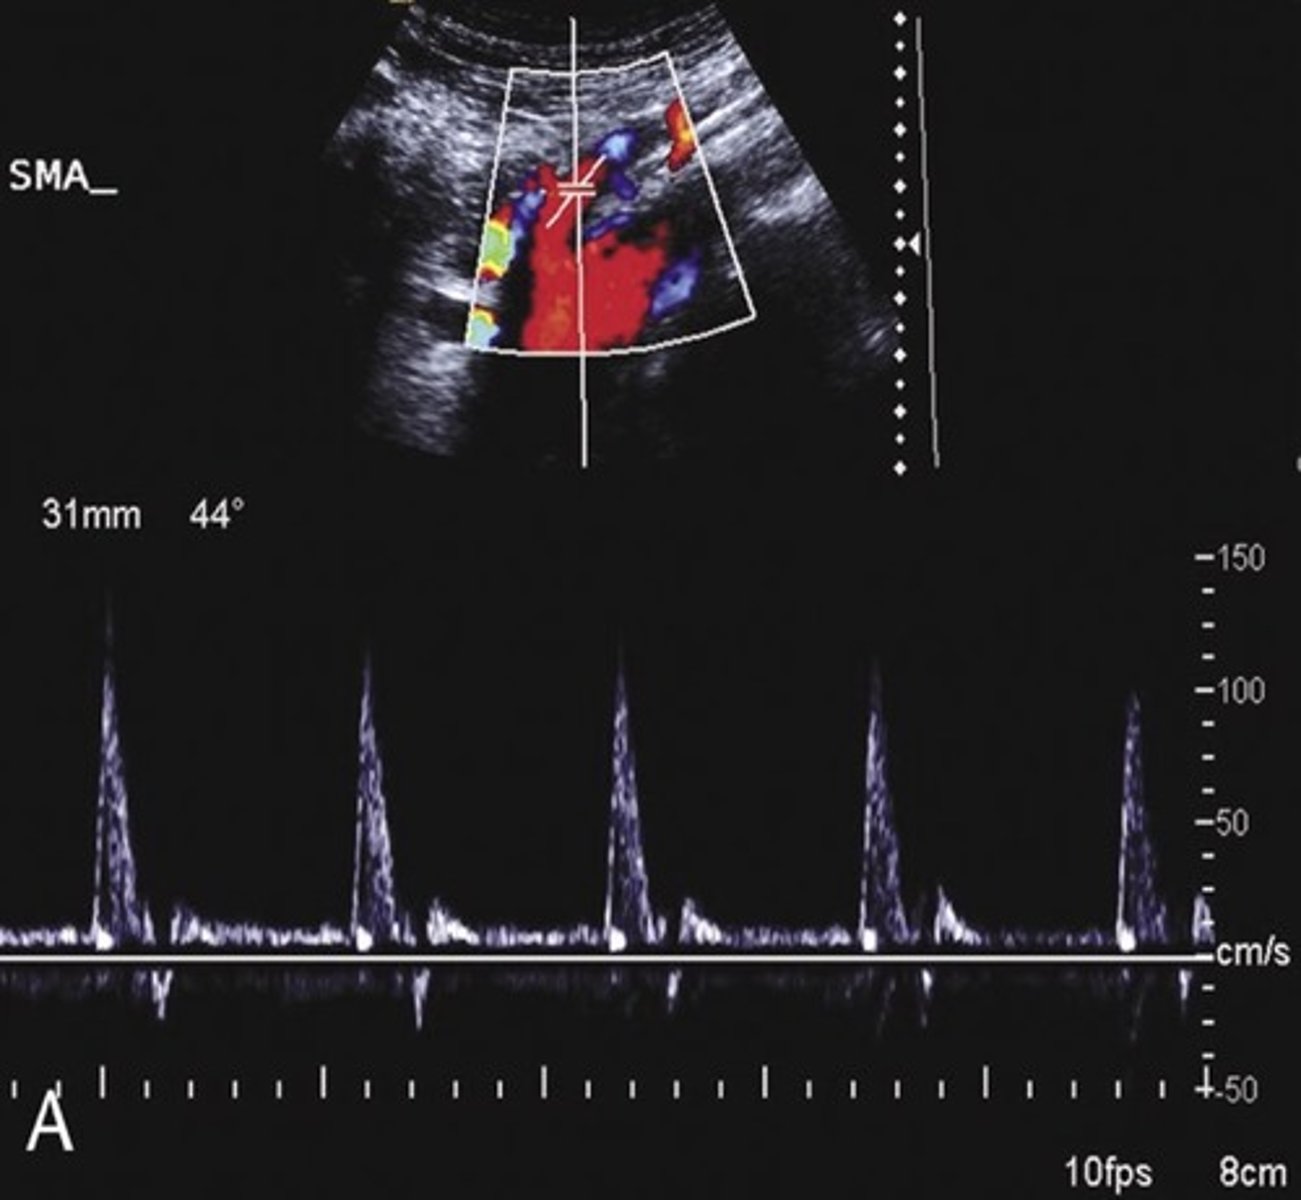

Pre-Prandial SMA Doppler

Post-Prandial SMA Doppler